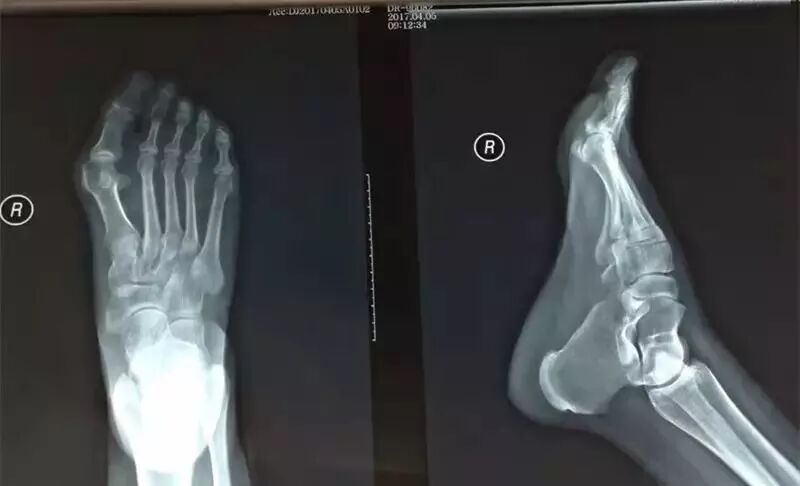

胡某,女,53岁,右足行走疼痛3月,加重半月余。查体:右足拇外翻,横弓塌陷,右第二趾上翘、下方胼胝,第二跖趾关节环形轻度压痛。

诊断:

1

右第二跖趾关节滑膜炎

2

右第二跖趾关节错缝

3

右足胼胝

4

右足横弓塌陷

5

右足拇外翻